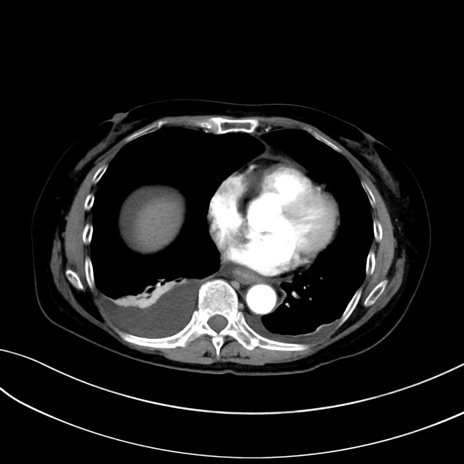

症例13 CT(横断像)1日半後